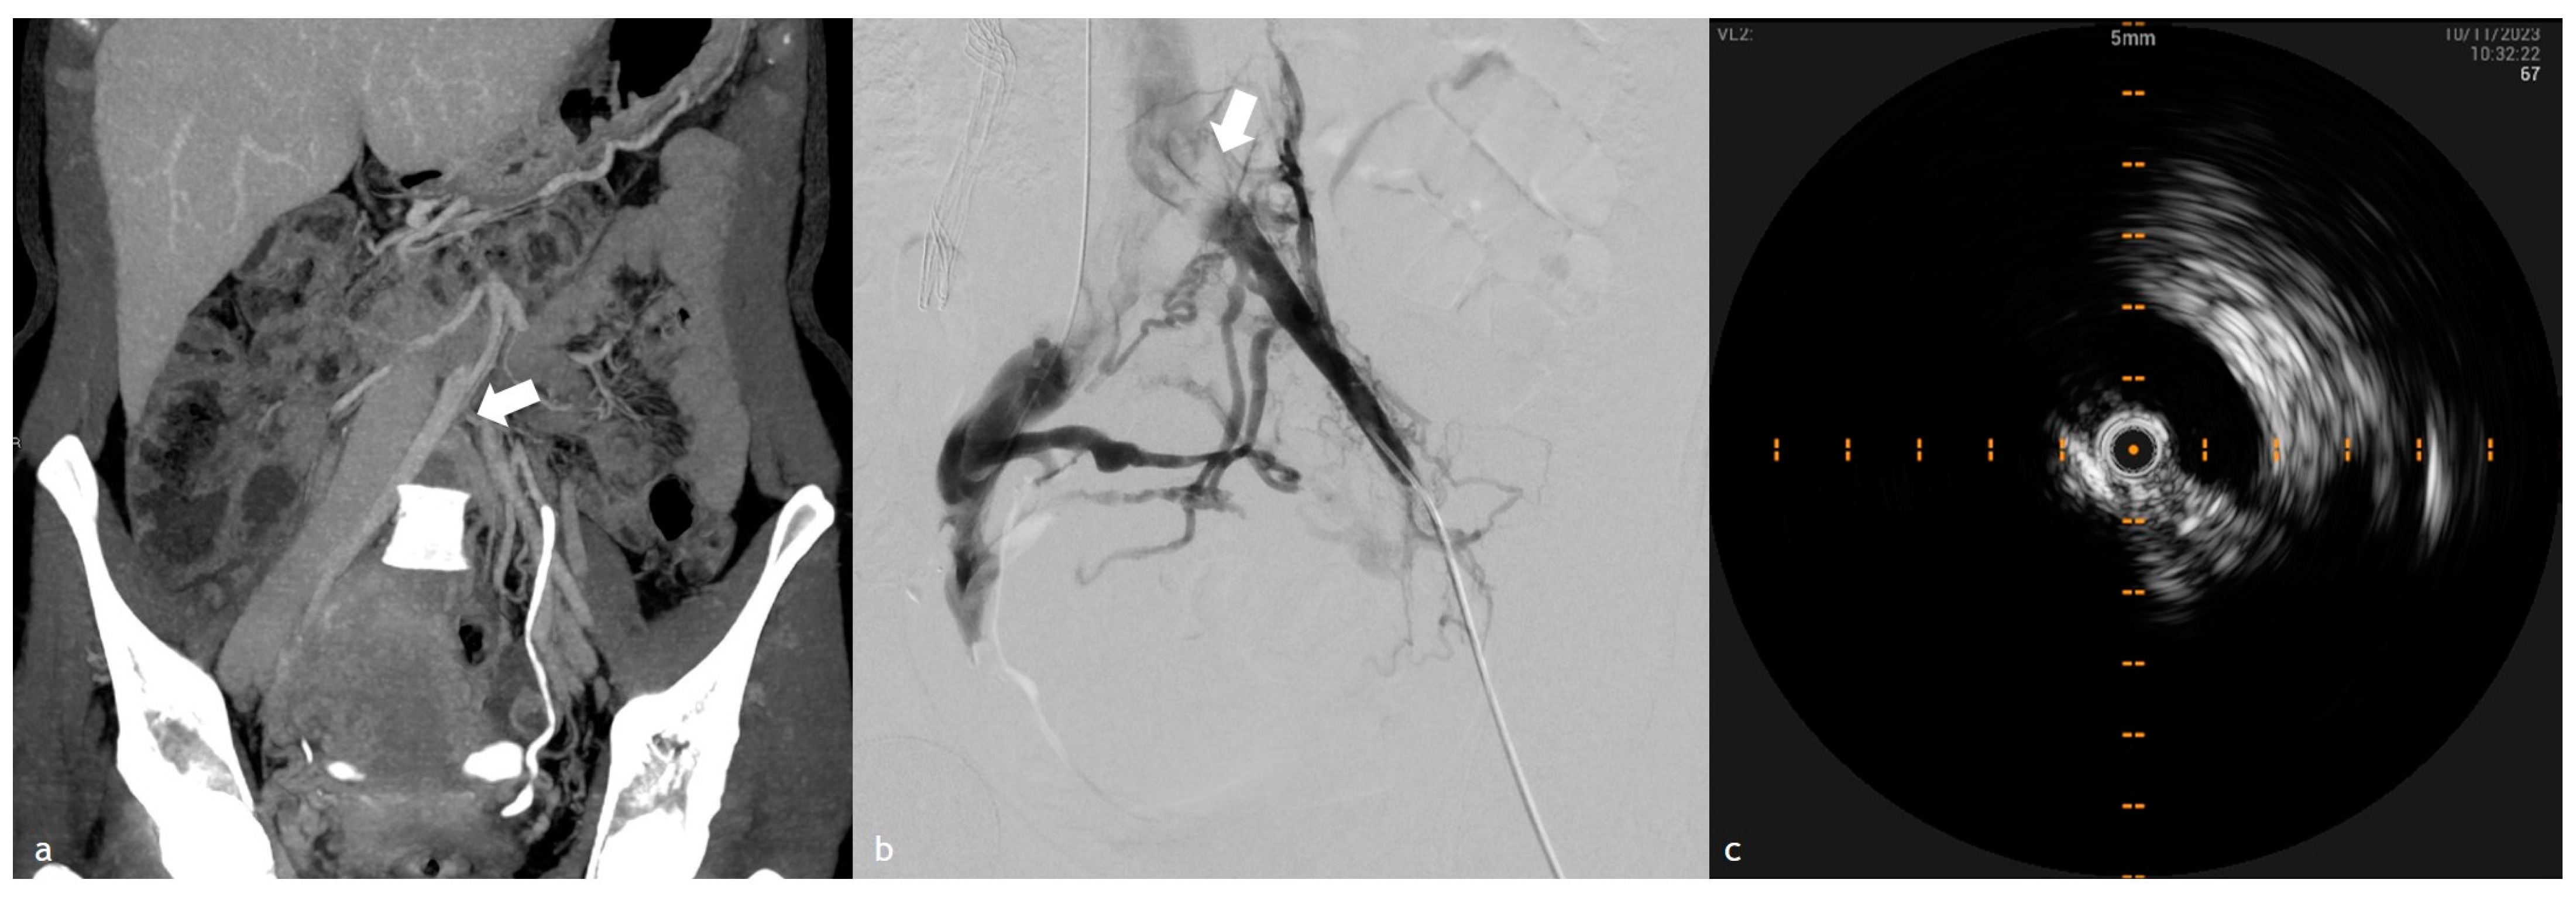

3. IVUS in Acute Lower Extremity DVT